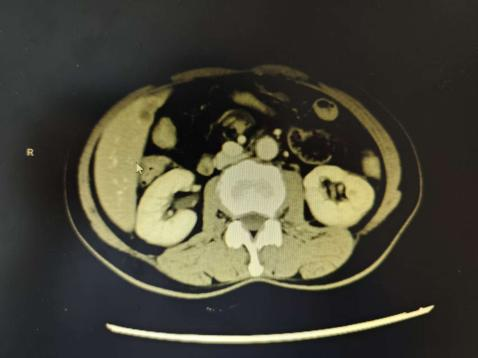

▲肝脏转移灶影像